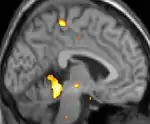

![]() | ![]() | ![]() |

| Positron emission tomography (PET) shows brain areas being activated during pain. | ||

Positron emission tomography (PET) scans indicate the brain areas which are activated during attack only, compared to pain free periods. These pictures show brain areas that are active during pain in yellow/orange color (called "pain matrix"). The area in the center (in all three views) is specifically activated during CH only. The bottom row voxel-based morphometry (VBM) shows structural brain differences between individuals with and without CH; only a portion of the hypothalamus is different.[36]